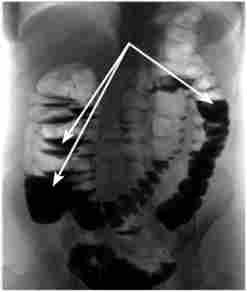

При сумнівних результатах оглядової рентгенографії живота або при проведенні консервативного лікування та динамічного спостереження вдаються до рентгеноконтрастним методам дослідження шлунково-кишкового тракту: оцінці пасажу барієвої суспензії по кишечнику (рис. 23.5) і ирригоскопии. Перший метод здійснюється наступним чином: пацієнтові дають випити 100 мл рідкої барієвої суспензії або вводять її по шлунковому зонду. Оглядовий знімок живота роблять через 4, 6 і 8 год. У здорової людини контрастну речовину досягає товстої кишки через 4-5 год після прийому. Затримка контрастної речовини в тонкій кишці довше цього часу свідчить про наявність непрохідності. Крім цього, контрастну речовину допомагає виявити діаметр і поперечну смугастість (складчастість) тонкої кишки. Іррігоскоіія може бути інформативною тільки при товстокишковій непрохідності. Вона частіше застосовується при плановому обстеженні хворих з підозрою на пухлину товстої кишки.

Рентгеноконтрастне дослідження живота

Мал. 235. Рентгеноконтрастне дослідження живота.

Оцінка пасажу барієвої суспензії по кишечнику.

Барій в тонкій кишці, видно чаші Клойбера